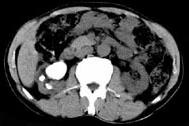

- 多项选择题男,53岁, 反复右侧腰部隐痛不适2年余,CT如图所示, 下列说法正确的是 ( )

A、右肾多发结石

B、右肾铸型结石

C、右肾钙化

D、右肾自截

E、部分肾盏有扩张积液